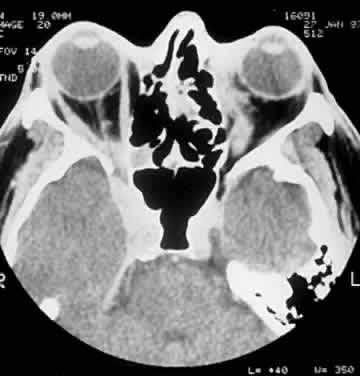

Computed tomography (CT) accurately demonstrates the molding of the mass to orbital structures, such as the globe and orbital bones, without bony erosion except in large cell lymphoma (Fig. 7). CT is used to localize the lesion, which tends to be unilateral and in both the intraconal and extraconal spaces. Lesions limited to the conjunctiva tend to be more benign with a better long-term prognosis, whereas those that extend into the orbit tend to be more malignant. Conjunctival lesions remain localized in 90% of cases, whereas orbital and lid lesions have a higher rate of systemic extranodal involvement.63 Lymphoid lesions of the lacrimal gland appear as a diffuse vertical expansion of the gland, which mold to both the globe and orbital bone without producing a bony fossa or erosion64 (Fig. 8). If the lesion extends beyond the orbital rim, the palpebral lobe of the gland is involved, and posterior or orbital lobe involvement appears as a straight line against orbital fat. Pleomorphic adenoma, on the other hand, appears as an oval, globular lesion with, in 80% of cases, adjacent bone changes caused by the firmer stroma of the tumor. Because epithelial tumors usually arise in the orbital lobe, extension beyond the orbital rim is not a feature.65 CT scan cannot distinguish between inflammatory and lymphoid lesions, because both lesions are homogeneous and enhance with intravenous contrast, and at biopsy, orbital lymphoid lesions are pink with a friable texture caused by the absence of stroma.66–68 The subtype and malignancy of the lesion can only be determined morphologically. The following subtypes of B-cell nonHodgkin's malignant lymphoma—extranodal B-cell marginal zone lymphoma, follicle center cell lymphoma, small lymphocytic lymphoma, lymphoplasmacytoid lymphoma, mantle cell lymphoma, large cell lymphoma, and Burkitt's lymphoma—are discussed in the approximate order of frequency with which they occur in the orbit.

Fig. 8. A CT scan, axial view, of a B-cell lymphoma localized to the anterior orbit bilaterally, with left lacrimal gland involvement and a normal adjacent lateral wall.